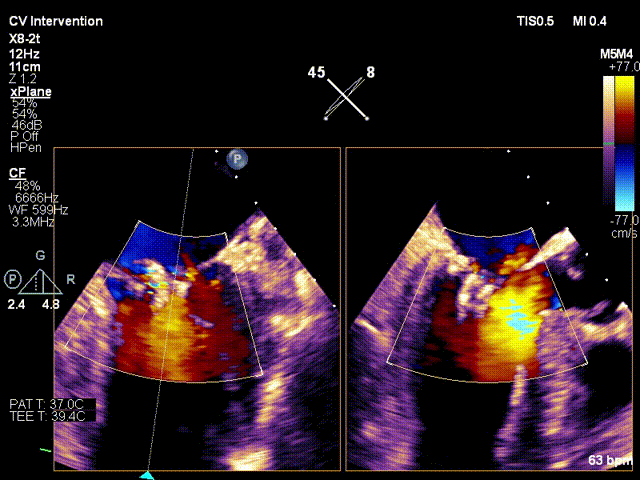

行TEE示:二尖瓣后叶脱垂合并重度反流(DMR4+)。左室后内乳头肌断裂,二尖瓣后叶腱索断裂。二尖瓣前叶长度17.6mm, 后叶有效长度6.1mm,二尖瓣后叶P2区脱垂,MVA 4.63cm²;PISA定量 EROA=0.72cm²。

心超参数:

患者镇静麻醉状态,呼吸机辅助呼吸,ECMO+IABP循环支持,因右侧股静脉入路ECMO占用,遂行左侧股静脉入路,顺利穿刺房间隔,经导管测定左房压力为:41/-3/14mmHg。之后迅速送入经导管二尖瓣钳夹系统,予XTR准确地捕获二尖瓣叶,于A2/P2区域完成夹合,MR4+反流即刻减少至2+;再予NTR定位与残余反流区域,完成二次夹合,反流即刻较少至微量。术中DSA及TEE评估夹合器稳定,遂退出钳夹系统。测定左房压13/-3/1mmHg,较前明显下降,血流动力学稳定,撤处ECMO,保留IABP,手术成功。